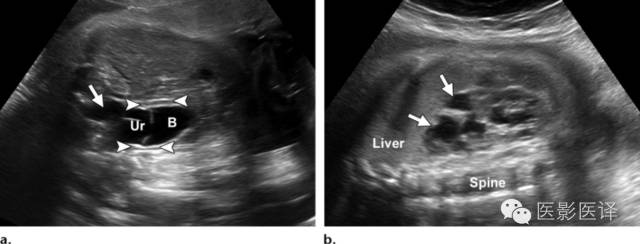

Nussbaum等最早将新生儿卵巢囊肿分为单纯性和复杂性。单纯性卵巢囊肿是圆的、无回声的、单房和薄壁的(图1)。它们更经常为单侧而非双侧、更经常为腹内而非盆腔内。单纯性囊肿内偶尔可见单个分隔(图2)。直径小于20mm的卵巢囊性结构被认为是成熟卵泡,为生理性而非病理性。直径大于20mm的囊肿则考虑为异常。“子囊”征描述的是囊内一个小的、圆形、无回声结构(图3)。既往报道认为这是卵巢囊肿的特征。【在一个23例囊性病变的研究中(包括新生儿、婴儿及儿童),11例发现子囊,占卵巢囊肿的82%(敏感度82%,特异度100%,阳性预测值100%),在其他囊性病变中未发现子囊,包括淋巴管瘤、肠重复畸形、肠囊肿、胎粪假性囊肿、阴道积液和脐尿管囊肿。】

图1:单纯性卵巢囊肿。冠状位胎儿超声图像显示一个边界清楚的薄壁无回声囊肿(箭),高于膀胱(B)位于腹内中线之外。注意脐动脉(箭头)在膀胱两侧。

图3:单纯性卵巢囊肿。(a)矢状位胎儿超声图像显示一个边界清楚薄壁腹内囊肿(箭头),其内可见一个子囊(箭)。囊肿位于膀胱(B)上方腹中线区。Uv=脐静脉。(b)同一病人轴位超声多普勒图像显示在薄壁卵巢囊肿中有两个子囊(箭头)